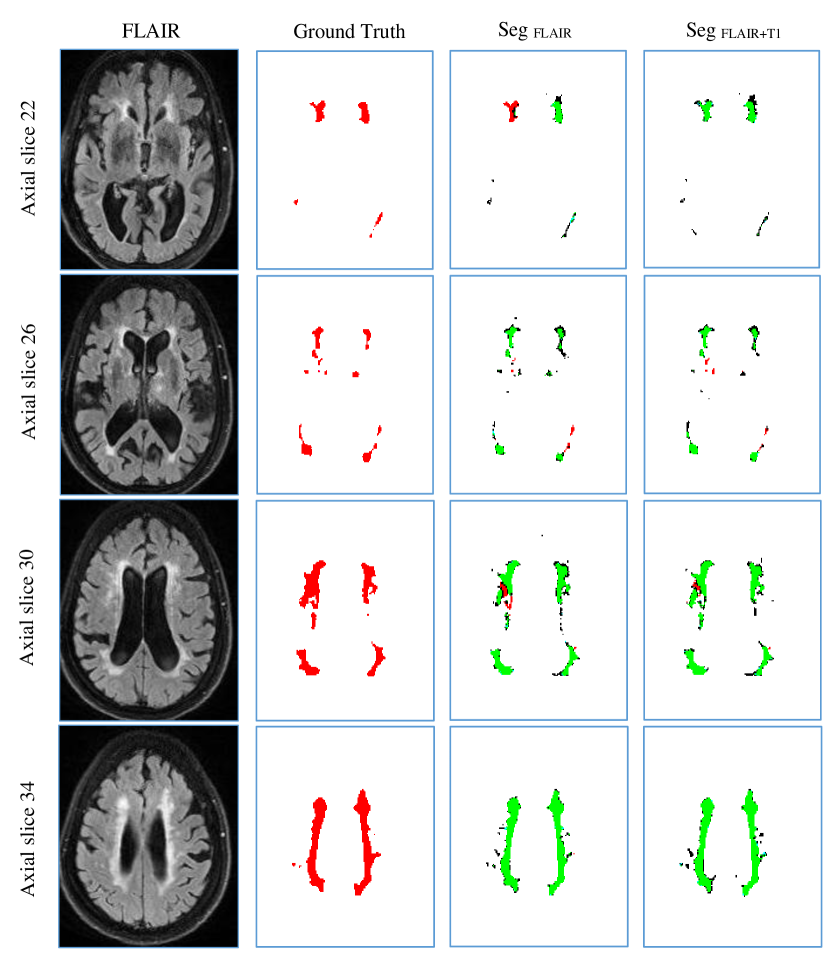

The T1 modality is known to provide a good contrast between the healthy tissues of the brain while FLAIR sequences are widely used to distinguish pathologies present in the white matter. Based on this, we assumed that these two modalities can provide complementary information for segmenting WMH. According to previous work (Dyrby et al., 2008), a combination of FLAIR and other modalities significantly improved the segmentation performance than using FLAIR alone. However, whether this combination improves the generalization capability to unseen scanner, has not been clearly investigated. We therefore analysed and presented a novel study for comparison in a cross-scanner-evaluation manner.

Table S2 to Table S4 in supplemental material report extensive results. They show that the combination of FLAIR and T1 slightly outperformed FLAIR alone on most of the metrics, suggesting T1 modality could provide useful information for detecting WMH. In Figure 10 we showed the segmentation results of a case from Singapore tested by the model trained on Utrecht and GE3T. We observed that some false negatives were removed by using the combination of FLAIR and T1 after comparing the column SegFLIAR+T1 and SegFLIAR, suggesting T1 provided complementary information on judging WMH. We further performed Wilcoxon signed rank test on the 60 cases. The improvements on H95 and F1-score were significant, giving p-values smaller than 1 .